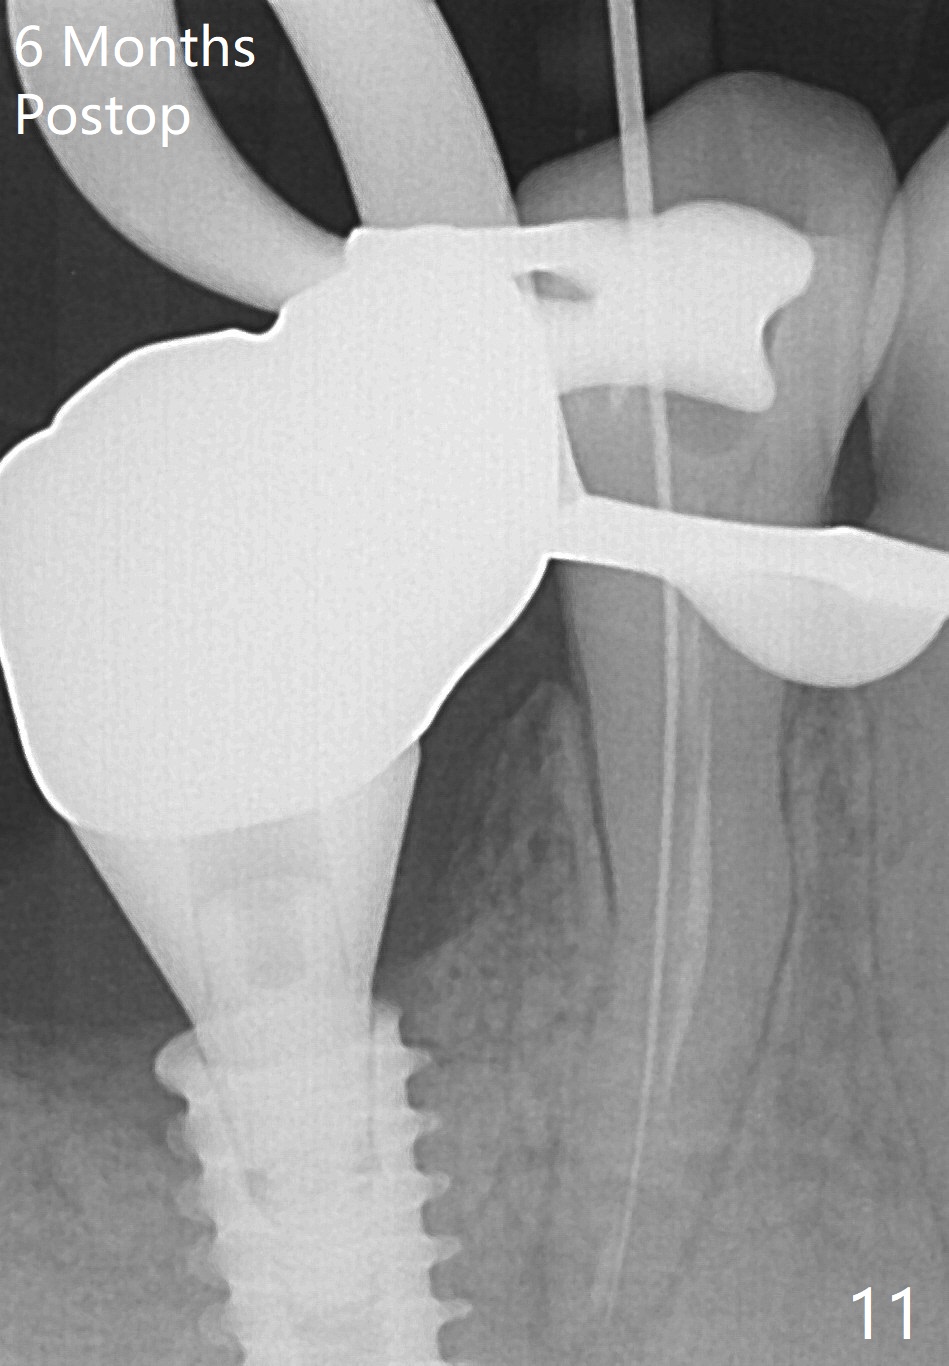

Bone graft seems to sink down and becomes denser 3 months postop (Fig.6 arrow). The bone continues being denser 5 months postop (Fig.7). There is periapical radiolucency of the tooth #29 (^). RCT is done (Fig.8). The pain persists 2 weeks postop (Fig.9,10). There is no missing canal (Fig.9). The apex is close to the implant (Fig.9 *). Apicoectomy will be performed if needed. It appears that the implant is also placed buccal (Fig.10 <) and/or the implant too large for the site. Therefore there should be a 2-3 mm buccal gap before and after implant placement. Separation and reflection of the buccal flap allows better visibility. The pain persists 1 month post RCT and 6 months post implant placement. RCT retreatment is initiated (Fig.11,12) with placement of Calcium Hydroxide paste after redebridement with 30/.04 rotary file at 23.5 mm (.5 mm longer than the earlier RCT, Fig.13). RCT retreatment finishes with apparent transportation and extrusion in 4 weeks (Fig.14,15), followed by apicoetomy (Fig.16,17) (20 days later)). Discomfort remains 2.5 months postop (Fig.18). Keep watching.